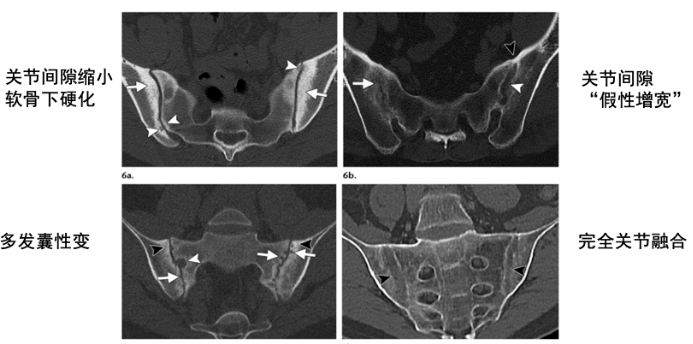

X线:对骶髂关节病变有诊断和分级意义,但只能检测慢性骨变化,这种变化通常需要几年时间才能变得明显,会导致诊断延迟。典型的骶髂关节炎可表现为关节面模糊、软骨下骨密度增高、骨质侵蚀、囊性变,随病情进展,可出现关节间隙狭窄甚至融合。

CT:结构变化比X线更灵敏,可更详细地评估骶髂关节病变,较MR可更好地评估关节韧带部分的骨质增生。